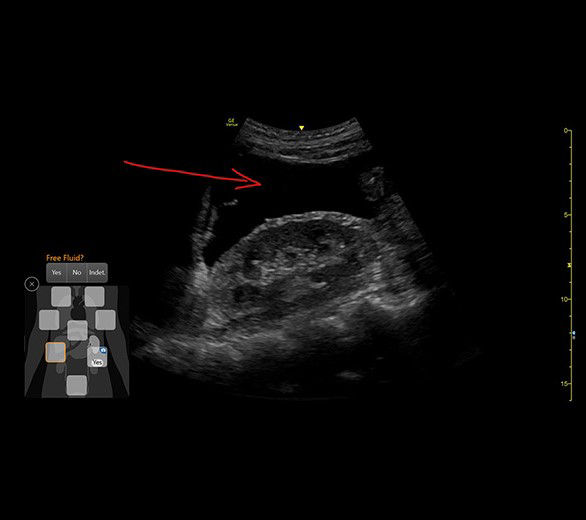

EFAST TOOL

A structured approach to trauma assessments

The eFAST tool helps you to quickly assess patient status, from internal bleeding to pneumothorax, and helps drive consistency from user to user by providing a way to reference multiple exams over time.

• Scan different zones sequentially, in a predetermined order, or in any order you desire.

• Document findings with single keystrokes and touch screen controls.

• Store images to a specific body zone by using a visual anatomical diagram, with next step recommendations provided.

• Label each zone with the relevant finding while scanning.

• View a summary review screen during or after the exam, showing the stored images superimposed over the anatomical diagram.

eFast-desktop